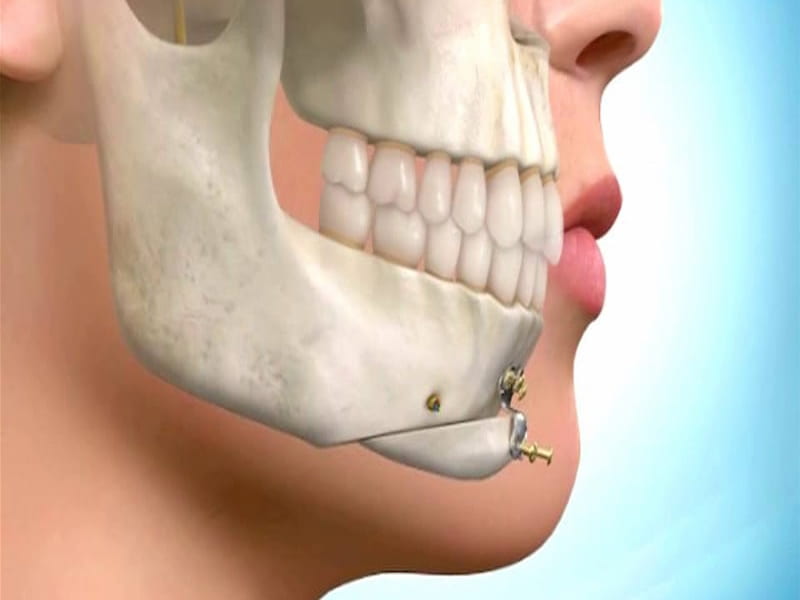

ایمپلنت و جراحی فک

ایمپلنت و جراحی فک باعث ایجاد یک راه حل دایمی برای مشکلات دندانی مانند دندانهای کمیاب یا قابل ترمیم نیست.

لازم به ذکر است که جراحی فک و استفاده از ایمپلنت دندانی یک روش جدید و پیشرفته است که در بسیاری از موارد بهبود وضعیت دندانها و جلوگیری از مشکلات بیشتر بسیار مفید است.

مشخصات ایمپلنت و جراحی فک